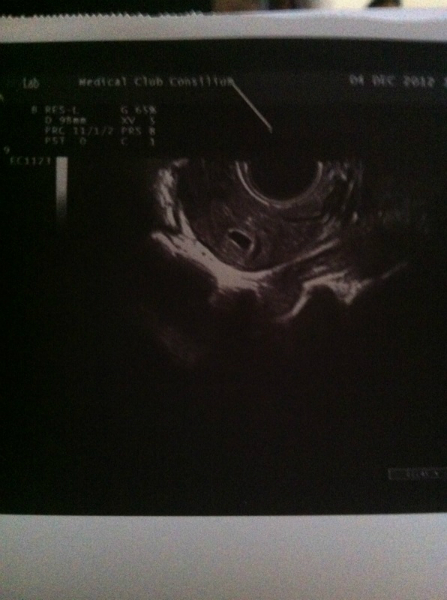

Привет мои хорошие))) Пугали нас ВБ как я ранее писала!! Но мы всем доказали что с нами все хорошо и никакой внематочной быть не может))) Сегодня было 3-е узи...нас долго искали и даже сначала сказали что НЕТ!!(( но под конец мы решили всех обрадовать и показались мамуле)))) ПЯ: 6мм...срок 4 недели поставили))) Я летаю на крыльях)))) Спасибо Господу Богу за мою бусинку...всю ночь молилась за нее!!!!! Девочки,не ходите рано на узи!!!! И не в коем случае не отчаивайтесь и верьте до конца!!!!))) Всем хочушкам скорейших //,а всем беременяшкам легкой Б и родов)))

А вот и мы: